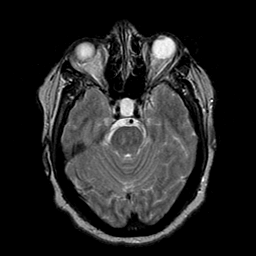

Cerebral hemorrhage, MR Study mr-t2 -- Slice #8

[Home][Help][Clinical] Slice 8